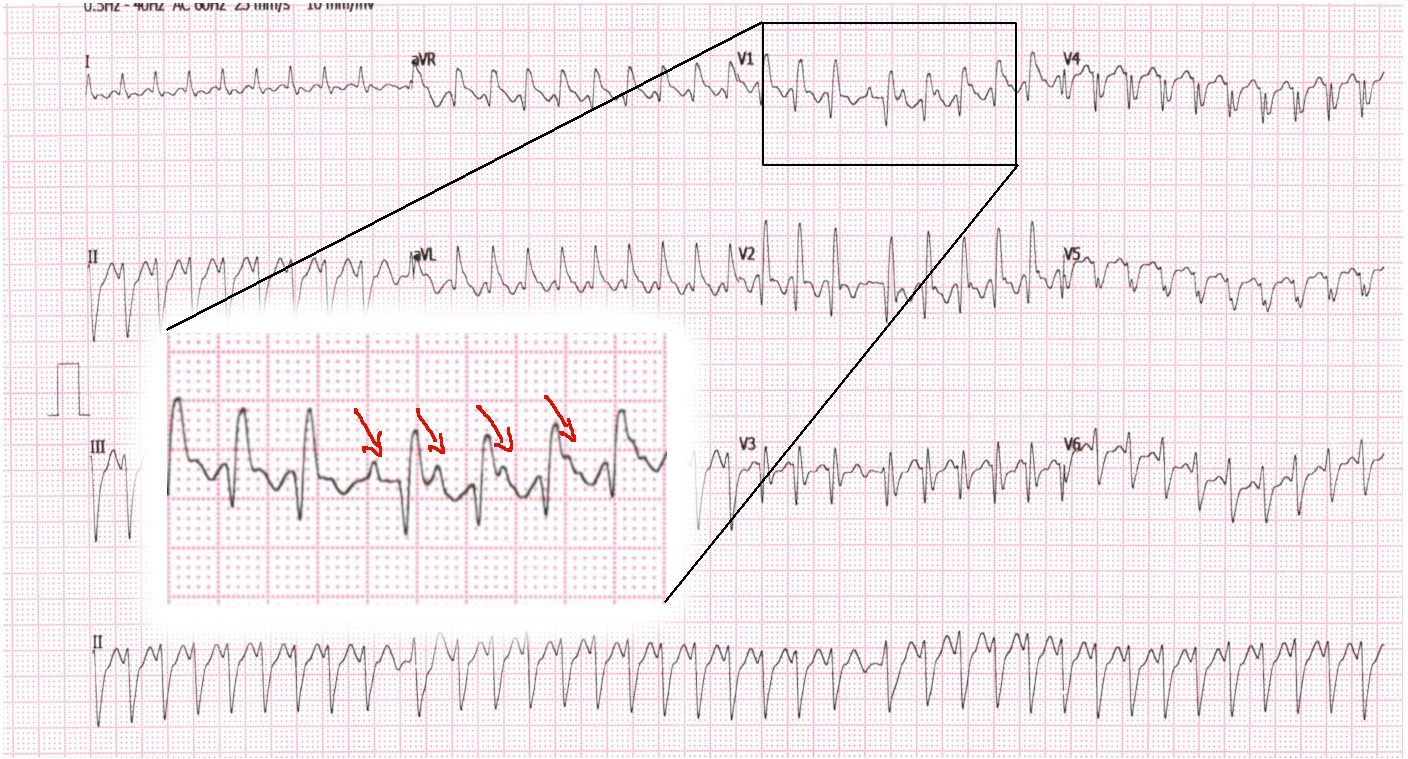

54 M, known CAD - old AWMI

kumar old mi sustained VT_001.jpg

60 M, old AWMI

RAMADASS awmi  svt CHANGES001.jpg

Adenosine

RAMADASS awmi  svt CHANGES002.jpg